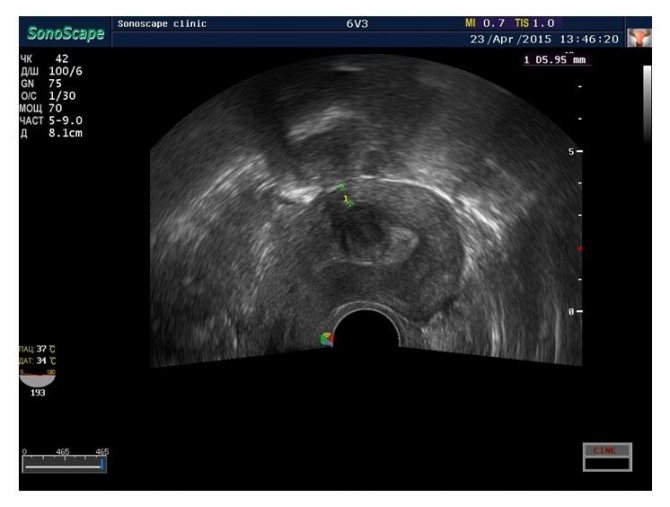

- Ультразвуковое исследование (УЗИ). Проводится с целью определения локализации и структуры миомы.

- Трехмерная эхография. Показание к проведению – точное выявление локализации и размеров миоматозных узлов.

- Допплерография. Проводится для оценки интенсивности кровотока в области опухоли, что помогает определить прогноз заболевания.